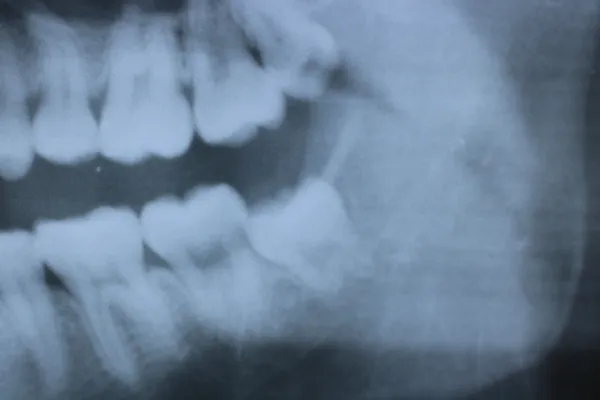

7親知らず

Case7